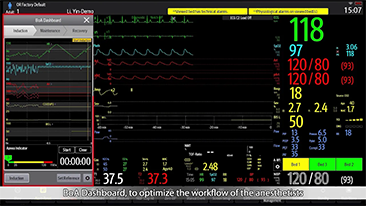

Mindray? ??? ??? ?? ??? ???? ??? ?? ??? ??? ????? ??? ????. ?? ???? ZONE Sonography? ??? ???? ?? Resona 7? ??? ZST+ ???? ?? ?? ? ?? ??? ????? ?? ??? ??? ??? ? ?? ????.

?? Resona 7? ???? ??? ?? ???? ??? ??? ???? ??? ?? ???? V Flow? ?? CNS ??? ?? 3D ??? ???? ?? ???? ?? ??? ?? ?? ?? ??? ??????. ???? ??? ??? ?? ?? ??? ??? ?? ?? ??? ??? Resona 7? ??? ???? ???? ??? ??? ??? ????.